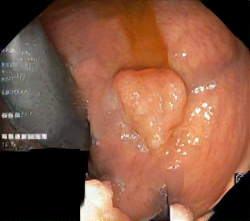

We have used a polyp dataset published with HyperKvasir dataset [51], which consists of polyp findings extracted from endoscopy examinations. HyperKvasir contains polyp images with corresponding segmentation masks annotated by medical experts. We use only this polyp dataset as a case study because of the time and resource-consuming training process of the SinGAN-Seg pipeline. However, the SinGAN-Seg model and pipeline can be used for any segmentation dataset.

A few sample images and the corresponding masks of the polyp dataset in HyperKvasir are shown in Fig 2. The polyp images are RGB images. The masks of the polyp images are single-channel images with white () for true pixels, which represent polyp regions, and black () for false pixels, which represent clean colon or background regions. In this dataset, there are different sizes of polyps. The distribution of polyp sizes as a percentage of the full image size is presented in the histogram plot in Fig 3, and we can observe that there are more relatively small polyps compared to larger polyps. Additionally, a subset of this dataset was used to prove that the performance of segmentation models trained with small datasets can be improved using our SinGAN-Seg pipeline, and the whole dataset was used to show the effect of using SinGAN-Seg generated synthetic images instead of a large dataset which has enough data to train segmentation models. In this regard, this dataset was used for two purposes: